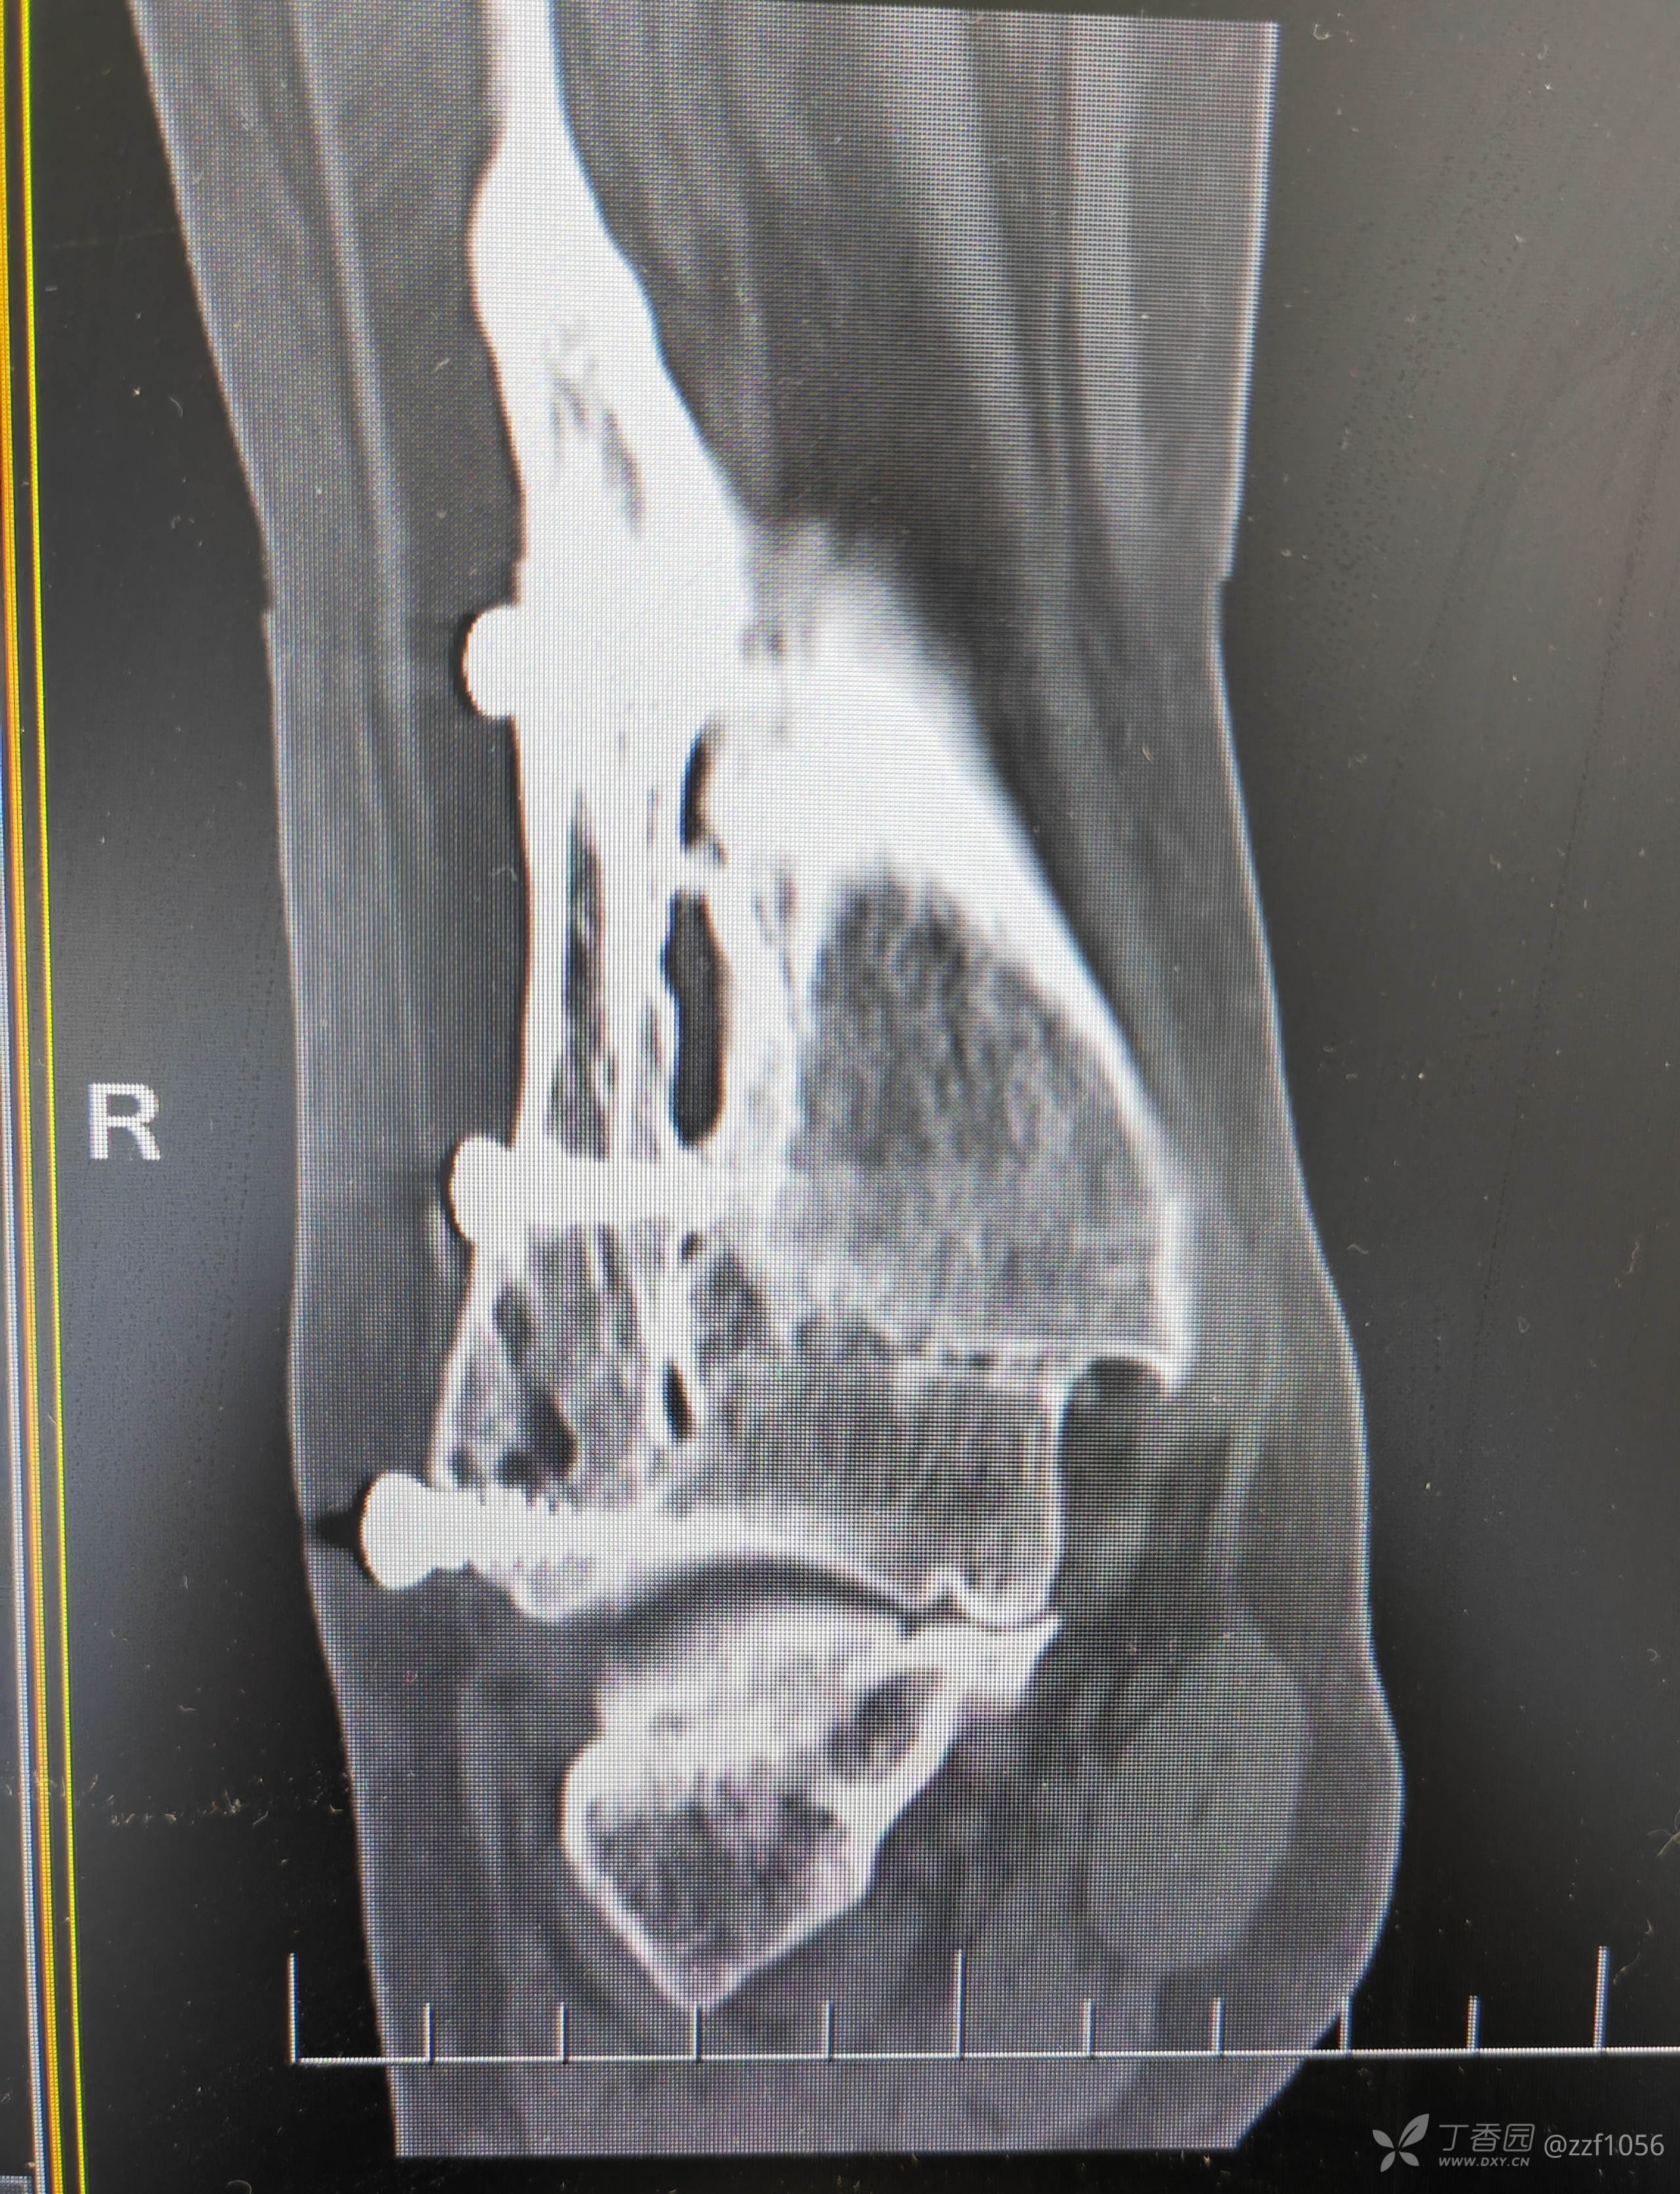

入院诊断:右踝关节骨折术后畸形融合,内固定存留

从骨折畸形愈合形态应该能推测当时接近于劈木机损伤,旋前外旋四度骨折。

看一下目前CT